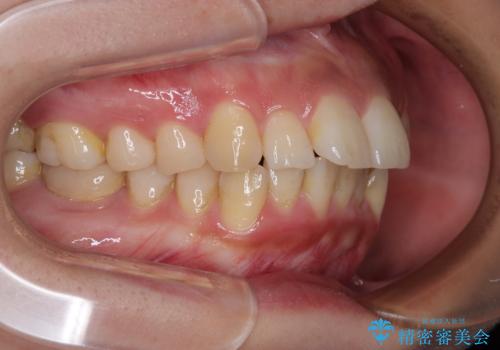

- 前歯のデコボコと口元の突出感を気にして来院された患者様です。

上下前歯がくちばしのように突出していたため、上下左右の第一小臼歯4本を抜歯し、ワイヤー装置にて矯正治療を行うこととしました。